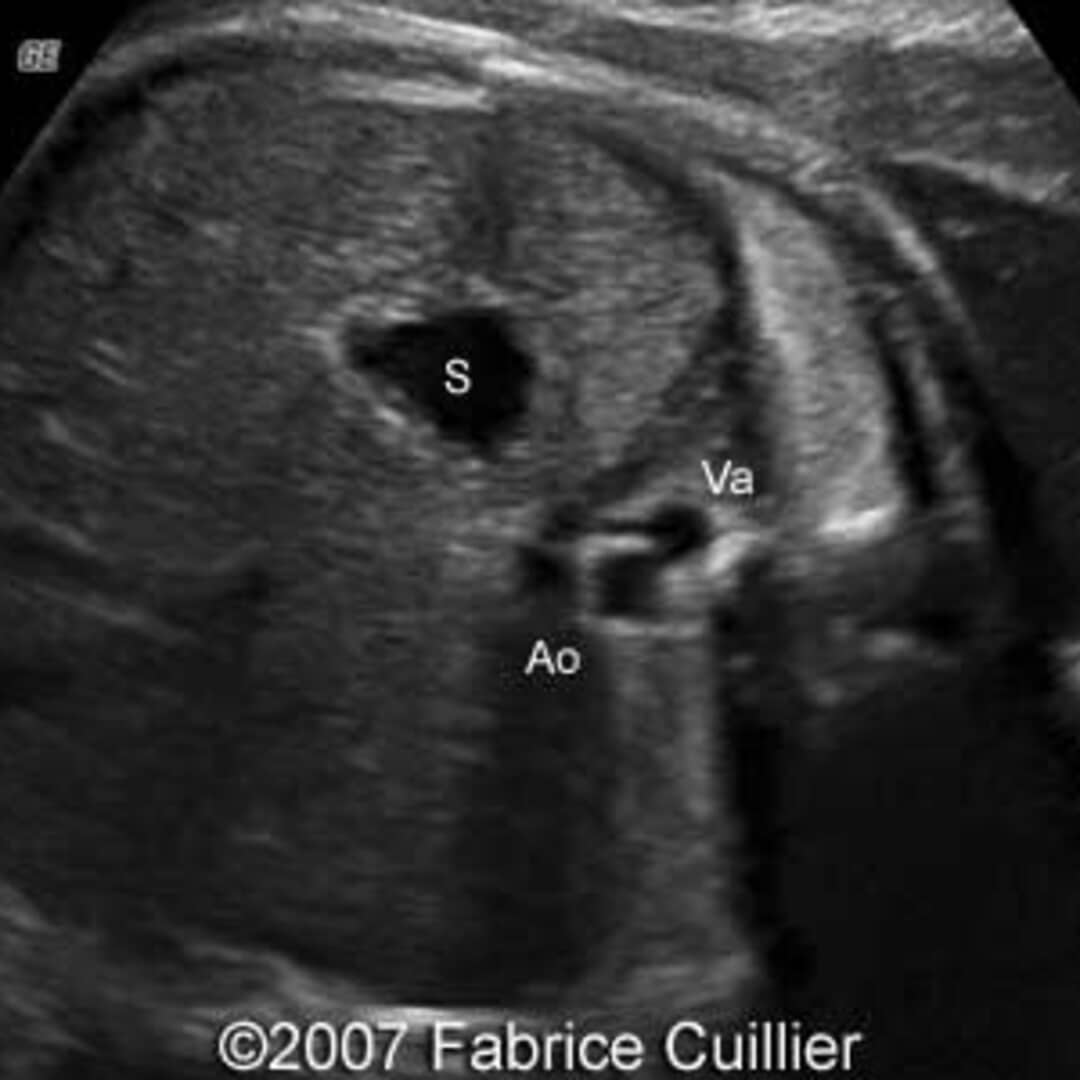

Diagnosis of situs inversus can be made using imaging techniques such as x-ray, ultrasound, CT scan, and magnetic resonance imaging (MRI).

The condition affects all major structures within the thorax and abdomen. Generally, the organs are simply transposed through the sagittal plane. The heart is located on the right side of the thorax, the stomach and spleen on the right side of the abdomen and the liver and gall bladder on the left side. The heart's normal right atrium occurs on the left, and the left atrium is on the right. The lung anatomy is reversed and the left lung has three lobes while the right lung has two lobes. The intestines and other internal structures are also reversed from the normal, and the blood vessels, nerves, and lymphatics are also transposed.

In rarer cases such as situs ambiguus or heterotaxy, situs cannot be determined. In these patients, the liver may be midline, the spleen absent or multiple, and the bowel malrotated. Often, structures are duplicated or absent altogether. This is more likely to cause medical problems than situs inversus totalis.